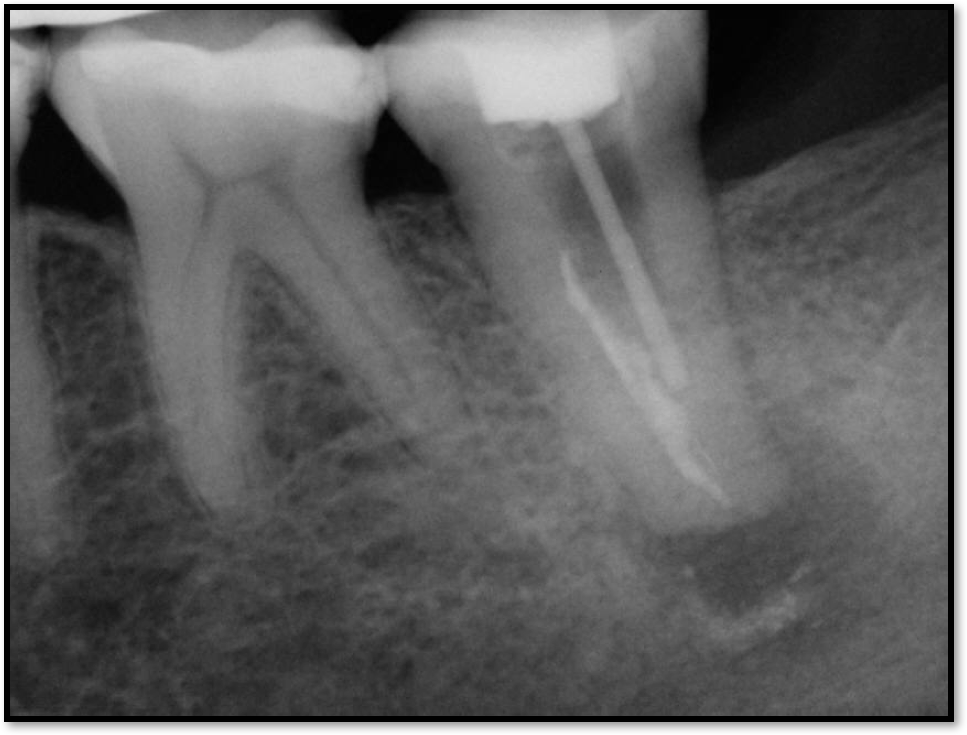

If a tooth stands alone, greater forces will be placed on it because it has no adjacent teeth to provide support. This situation will affect the decision-making process for placing a post. Figure 3 shows a tooth that was on an island and would be having three implants placed in front of it. The tooth would take a much greater beating than another tooth that had support proximally. Even though it had a good root canal, the clinician would need to account for whether the tooth would last until the implants integrated. Figure 4 shows a case that would quickly proceed to implants. The patient had a less-than-ideal bridge for over a decade, with decent endodontics and functionality. There was also an overhang on the premolar. The post was not ideal in this case because there was one distal canal and not all the gutta-percha was removed from it. An intimate fit should be the goal with the post and the walls. Whether using a threaded or non-threaded post, there should not be excess gutta-percha because it is not as solid as the tooth and will lead to greater movement. That movement on the tooth and bridge will create too much force and result in demise.

Fig 4. Case that quickly would proceed to implants.

Figure 4